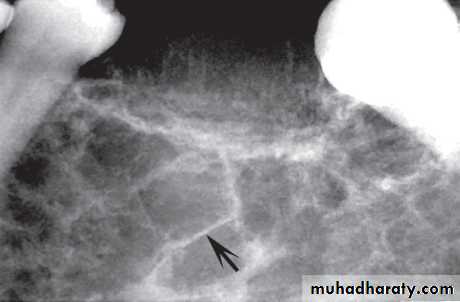

Odontogenic Fibroma and Myxoma

These very similar non-invasive tumors originate from the odontogenic connective tissue fibroblasts of the developing tooth germ, which produce either excessive fibrous collagen (fibroma) or excessive ground substance (myxoma). Radiographically they are often indistinguishable.Age: Young adults.

Site: Posterior mandible or maxilla.

Shape: — Multilocular

— Occasionally monolocular

— May be associated with a missing or unerupted tooth.

Outline: — Smooth and often scalloped

— Well defined with variable cortication

Radiodensity: Radiolucent with fine internal radiopaque septa or trabeculae often arranged at right angles to one another, producing an appearance sometimes described as resembling the strings of a tennis racket.